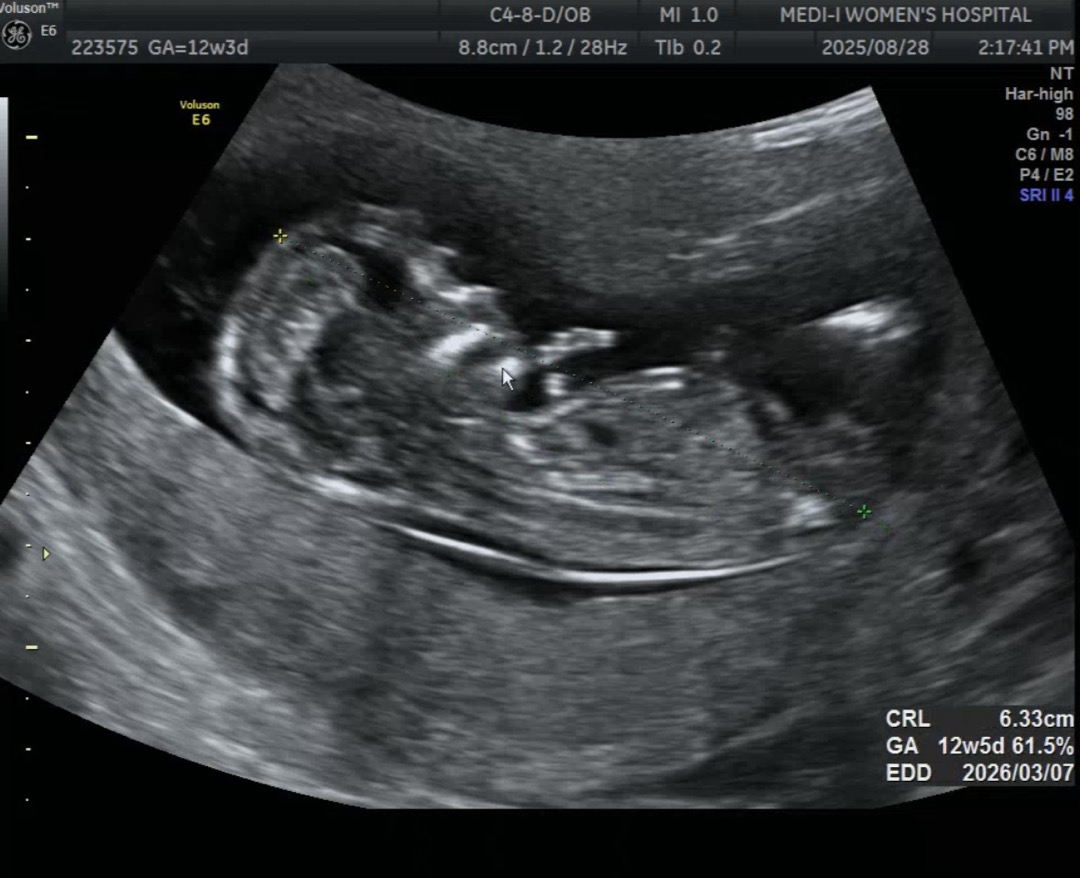

12주 3일차) 각도법 고수님들 도와주세여💕

오늘 병원 다녀왔어요..! 매의 눈으로 생식기를 훑어봤으나.... 전 아직 초보맘인가봐요ㅠㅠ 잘 모르겠네여ㅠㅠ 각도법 고수님들 딸일까요 아들일까요?! 투표 부탁드려요🙏🏻 둘째인데도 궁금한건 어쩔 수 없네요ㅠㅠㅠ